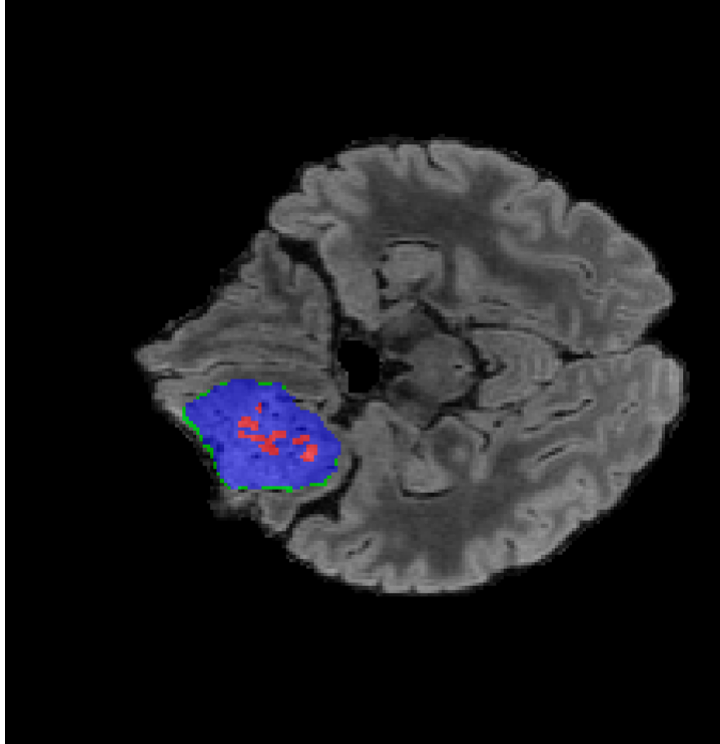

Tumour Information Preservation. For the brain tumor segmentation, we use a Swin UNETR model[28, 70], trained with random rotation, and intensity as data augmentation. On the test set with human ground-truth annotations (), the brain volumes generated from single slice input preserve the volume of the different tumour components (paired t-test, for all 3 classes). In Figure 4, we highlight the tumor profiles of the generated MRIs compared to the ground truth tumour profile. The real MRI Dice score in the test set is 85.15 while the generated MRIs from a single slice have a dice score of 83.09. This shows how the generated MRIs indeed preserve the tumor information and can act as an affordable and informative pseudo-MRI, before conducting an actual costly MRI examination in hospitals. More detailed results are provided in supplementary material.

Leveraging Context. Since we train on a predominantly cancerous brain dataset, one question that might arise is whether X-Diffusion generated MRIs preserve tumour information when the given inputs do not intersect with any tumour. We perform experiments varying the input slice index used to generate the 3D brain MRIs and measure the performance for input slices with no intersection with the tumour (not a single pixel with tumor label in the input slice). We also measure performance when only input slices are selected from tumor range. The Dice Scores of the random slices, no-tumour, and only-tumour are 83.09, 79.23, and 83.68 respectively. As can be seen here, the brain volumes generated from input slices with no tumour still preserve tumour information in reconstructed brain volumes despite a small drop in performance. This indicates that X-Diffusion is leveraging the context to preserve key information, such as tumor locations. This observation is consistent with how tumor segmentation models with global context [13] perform better than local-based U-Nets. More details are provided in supplementary material.